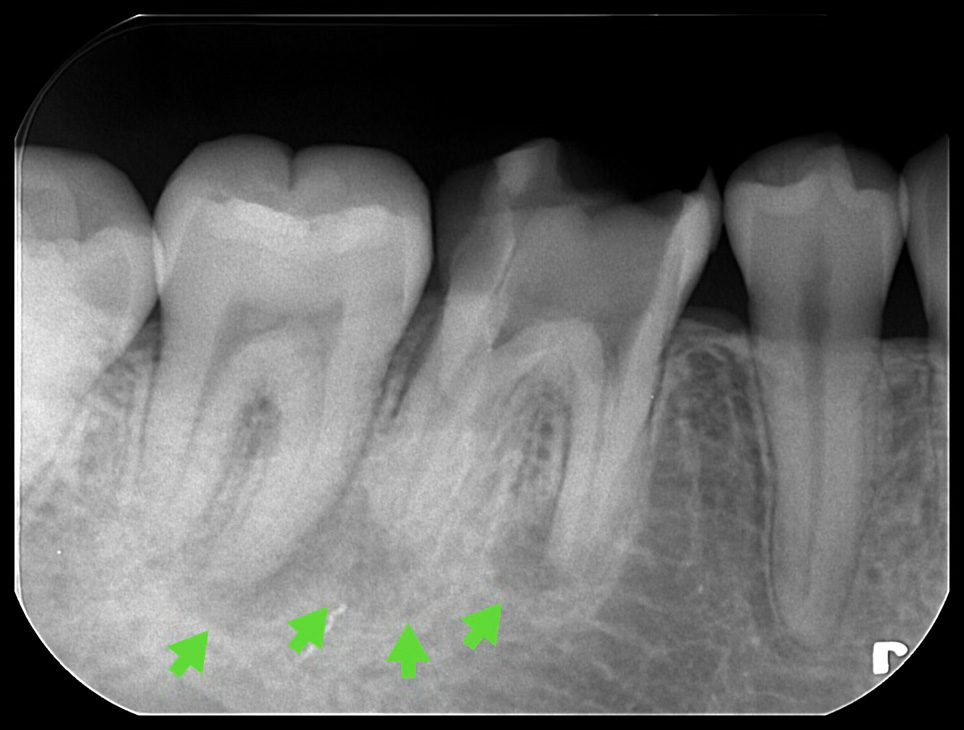

では次にレントゲン写真とCT写真の状態です。

レントゲン写真より、根の先の影(透過像)が後ろの奥の第二大臼歯のところまで広がっているように見えます。またレントゲンからの隣の歯と接する部分の歯が薄くなっています。

実際に透過像の範囲は第二大臼歯まで及んでおり、第二大臼歯の歯髄も死んでしまっている可能性も考えられました。そのため、コールドテストと言って歯に冷たい刺激を加えて歯髄の反応を確認しました。加えて歯髄電気診という微弱は電気刺激を第二大臼歯に加えたところ、歯髄は正常な反応を示したため、CT及び複合的な検査から第一大臼歯由来の透過像として、精密根管治療を開始しました。